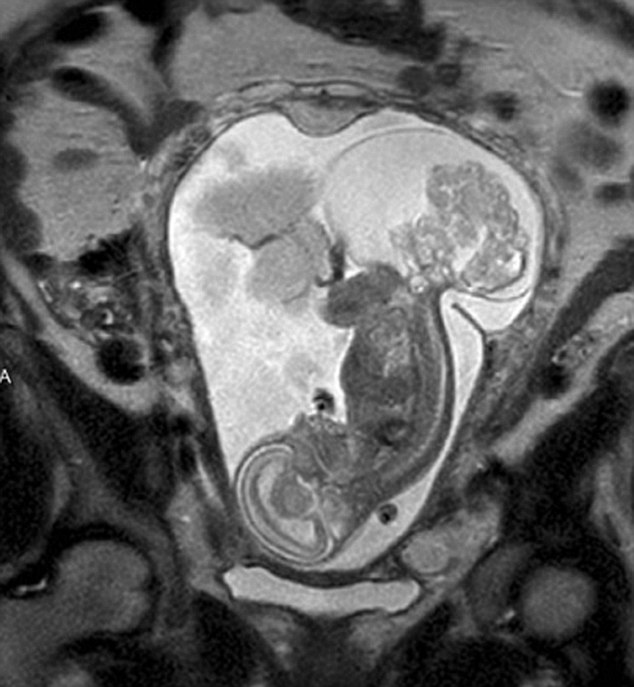

【環(huán)球網(wǎng)綜合報道】據(jù)英國《每日郵報》10月23日報道,美國得克薩斯州布蘭諾市的女子瑪格麗特·伯默(Margaret Boemer)懷孕16周時去做產(chǎn)檢,不幸被告知胎兒尾骨上長有腫瘤,她與醫(yī)生商量后決定先將胎兒取出進(jìn)行腫瘤切除手術(shù),再將其送回子宮繼續(xù)孕育。最終手術(shù)圓滿成功,12周后胎兒足月出生。

瑪格麗特稱自己當(dāng)時聽到產(chǎn)檢結(jié)果時十分害怕!搬t(yī)生說寶寶長了骶尾部畸胎瘤。我們很震驚,很害怕,因為我們根本不知道這個什么瘤到底意味著什么。”隨著時間流逝,腫瘤越來越大,胎兒滿23周時腫瘤已危及其性命。醫(yī)生告訴瑪格麗特,若想胎兒存活,只能將胎兒取出進(jìn)行手術(shù),然后再放回子宮,否則只能立即終止孕期。“這很容易做決定:讓腫瘤奪去孩子性命,或是給孩子存活的機會。我們當(dāng)然選擇后者。”瑪格麗特說。

醫(yī)生將胎兒取出20分鐘后,便放回母體子宮。12周后,寶寶足月出生,敻覃愄胤Q:“這可以說是她的第二次出生了。只要她有機會活下來,我愿意承受所有風(fēng)險。”(實習(xí)編譯:高睿 審稿:朱盈庫)